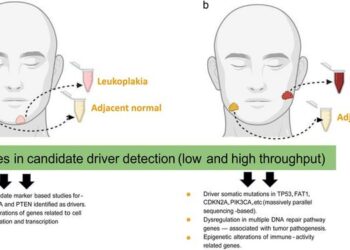

Progression of oral leukoplakia to cancer: importance on collection of leukoplakia and cancer tissues from disparate or same patients

Oral Leukoplakia (OLK) is recognized as a predominant potentially malignant oral epithelial lesion (PMOEL), posing significant risks due to its...